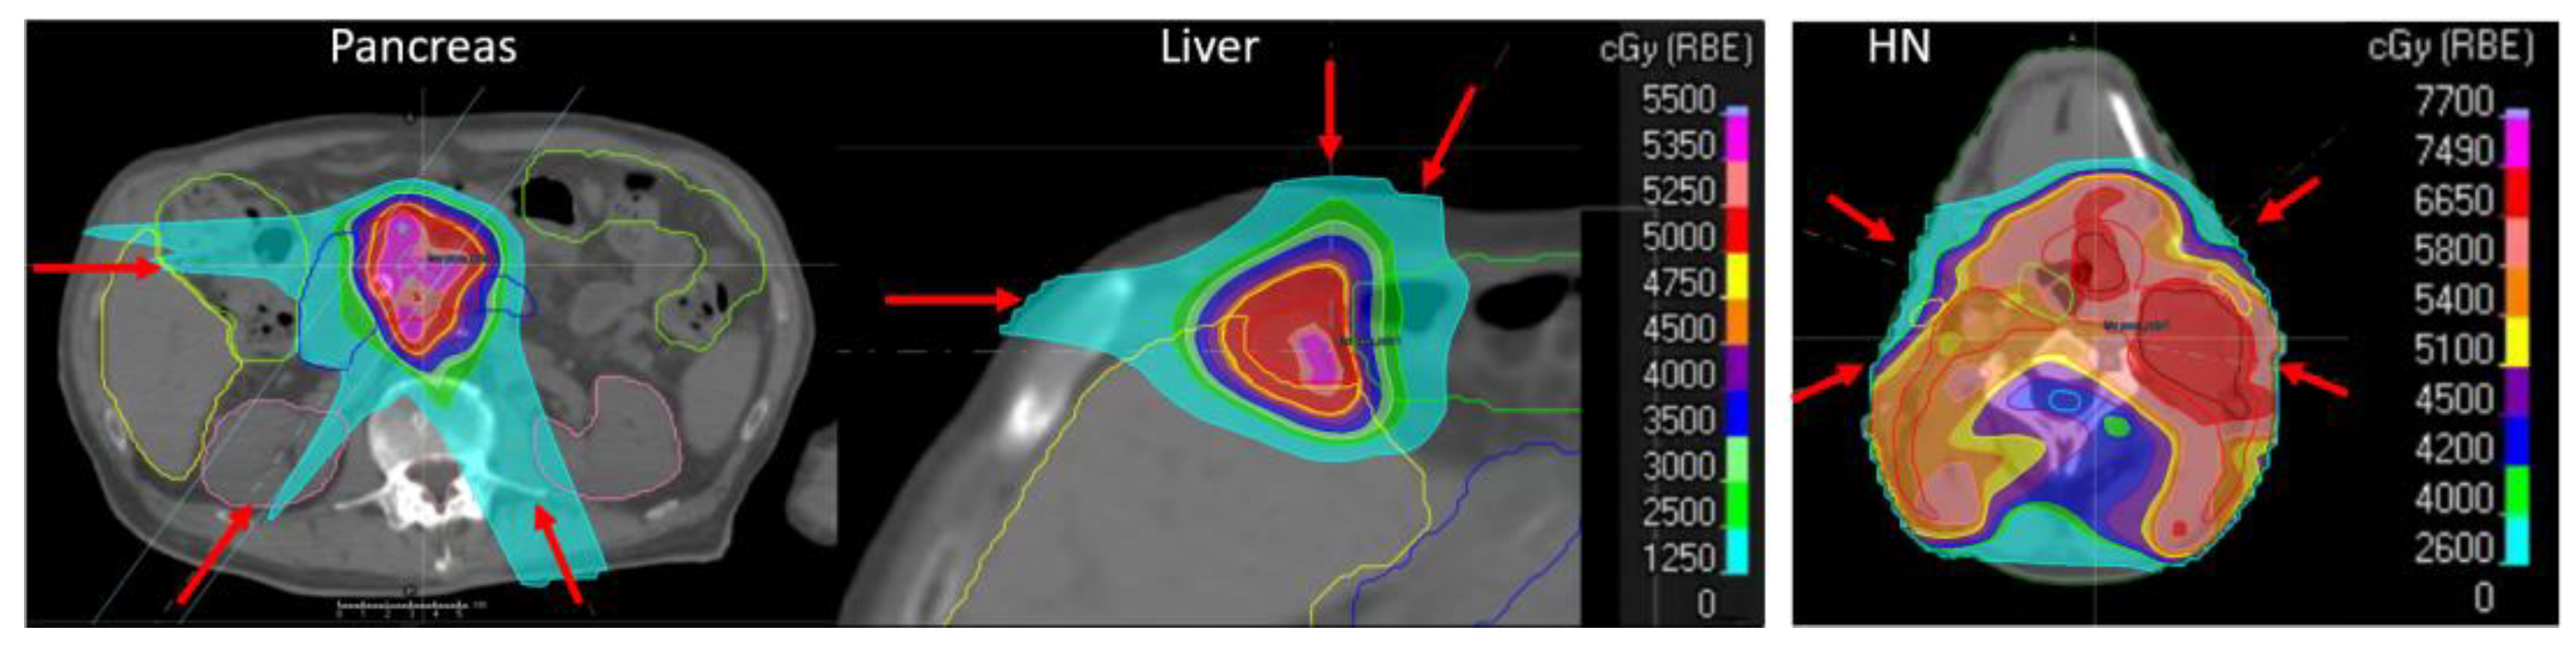

- Single-DIR adaptation:DIR-propagated structures were directly used for optimization without any manual corrections. Therefore, 3 different single-DIR adaptive plans were optimized on all replanning CTs, with structures deformed with Raystation, Plastimatch Demons, and Plastimatch B-spline.

- Multi-DIR adaptation:The same replanning CTs with the 3 different structure sets used for single-DIR adaptation described above were combined using the Raystation robust optimization function on multiple images and structure sets. This is the worst-case optimization [20], optimizing the plan using multiple images and structure sets in parallel.

- Conservative adaptation:Structures from the 3 different DIRs were combined. For pancreas and liver cancer patients, a stereotactic prescription was used, i.e., all organ constraints must be fulfilled, while target coverage is only the second priority. Therefore, for the conservative adaptation of these stereotactic prescriptions, the intersection of all propagated structures was used as the target structure, and the union for organs. In contrast, for HN patients with this prescription, the target coverage had a higher priority; therefore, the union of all propagated structures was used for the target and organs. The union and intersection of structures were calculated in Plastimatch and imported into Raystation for optimization.

- Probabilistic adaptation:Substructures were defined for each structure depending on how often a voxel was classified as part of the structure. If all 3 DIRs agreed that a voxel was a target, this voxel was included in the 100%-target substructure; if only two DIRs classified a voxel as a target, it belonged to the 67%-target substructure; if only one algorithm defined it as a target, it belonged to the 33%-target substructure. The 100%, 67%, and 33% substructures were calculated in Plastimatch and imported into Raystation. The optimization constraints of each structure were identical to those used for the planning CT, but the weights of these substructures varied according to the frequency that voxels were classified as a target or organ amongst the DIRs [21].

- Reference adaptation:All replanning CTs had “clinical” structures, manually contoured by a physician. These structures were directly used for the optimization of reference adaptive plans. These reference adaptive plans should result in the best possible treatment plan.